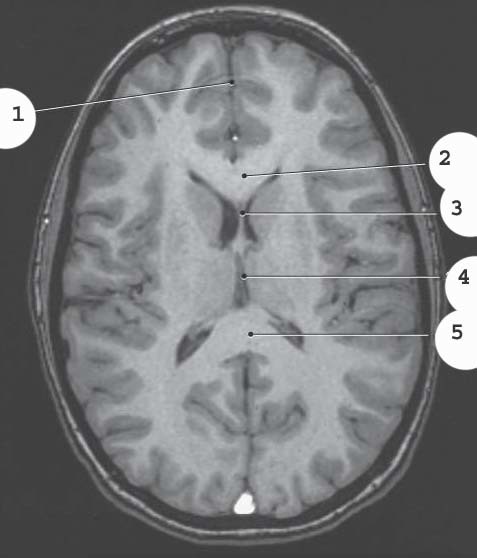

1

Lateral Vetnricle

2

corpus collosum genu

3

septum pellucidum

4

3rd ventricle

5

corpus collosum splenium